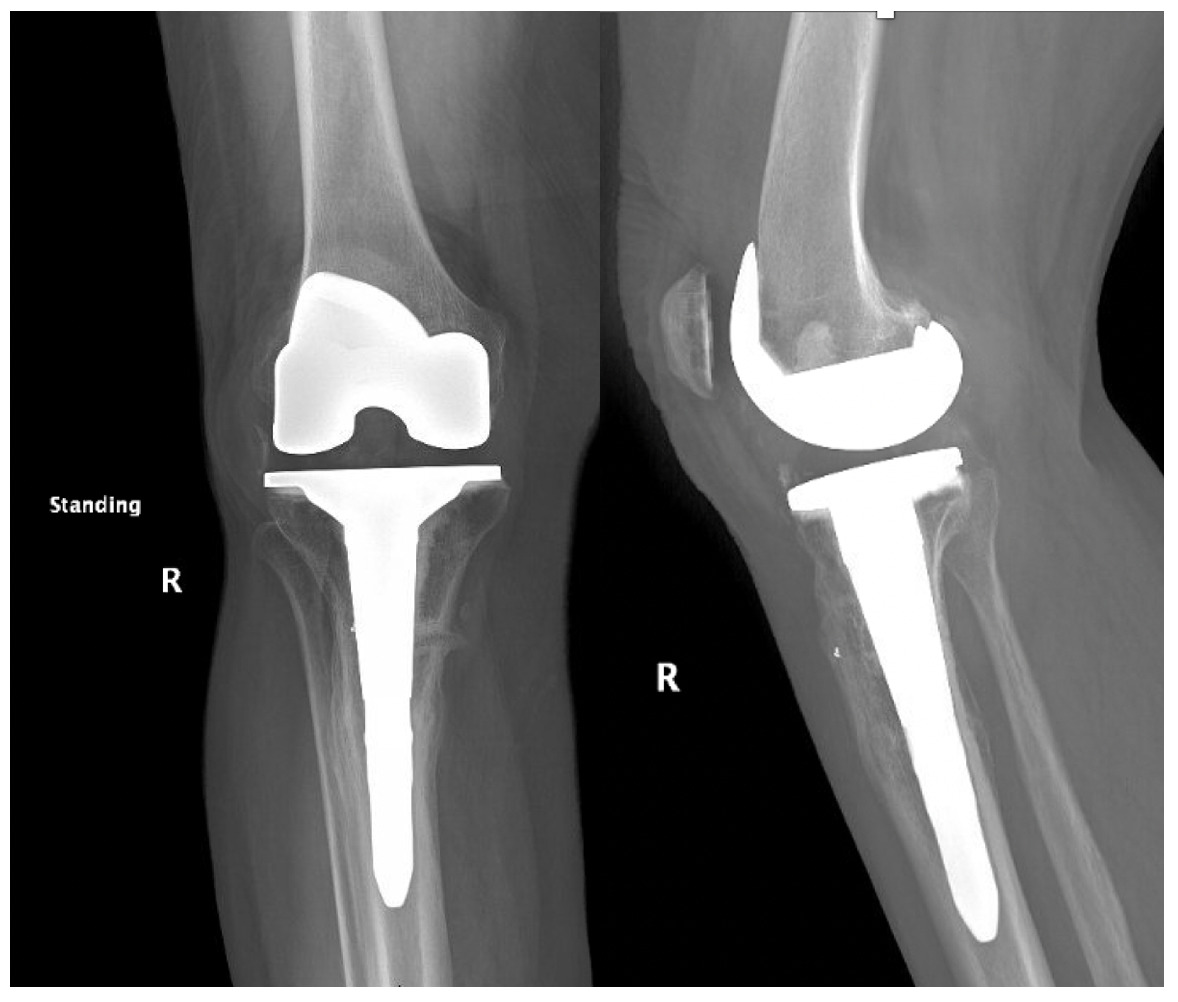

Trial components were inserted and demonstrated balanced flexion and extension gaps and central patellar tracking without the need for lateral release. The tibia was subsequently punched after confirming appropriate rotation for adequate patellar tracking. Final implantation proceeded with pressurized cement for the posterior-stabilized femoral component and the tibial baseplate under tourniquet insufflation. The diaphyseal press-fit stem was again confirmed to span the osteotomy by more than two cortical diameters under fluoroscopic guidance (Figure 4). Autogenous cancellous graft harvested from the femoral chamfer cuts was tightly packed into the osteotomy gap and along the medial cortex. The patella was resurfaced with a medialized polyethylene button.

The total estimated blood loss was 300 mL, and no transfusion was required. The patient tolerated oral intake on the evening of surgery, completed her first physiotherapy session the following morning, and ambulated fifty feet with a rolling walker while wearing the hinged knee brace locked in extension. Following ambulation, full length lower extremity films were re-obtained, demonstrating neutral mechanical hip–knee–ankle axis (Figure 5). She was discharged home on post-operative day two with acceptable pain control and an incision that was clean, dry, and intact.